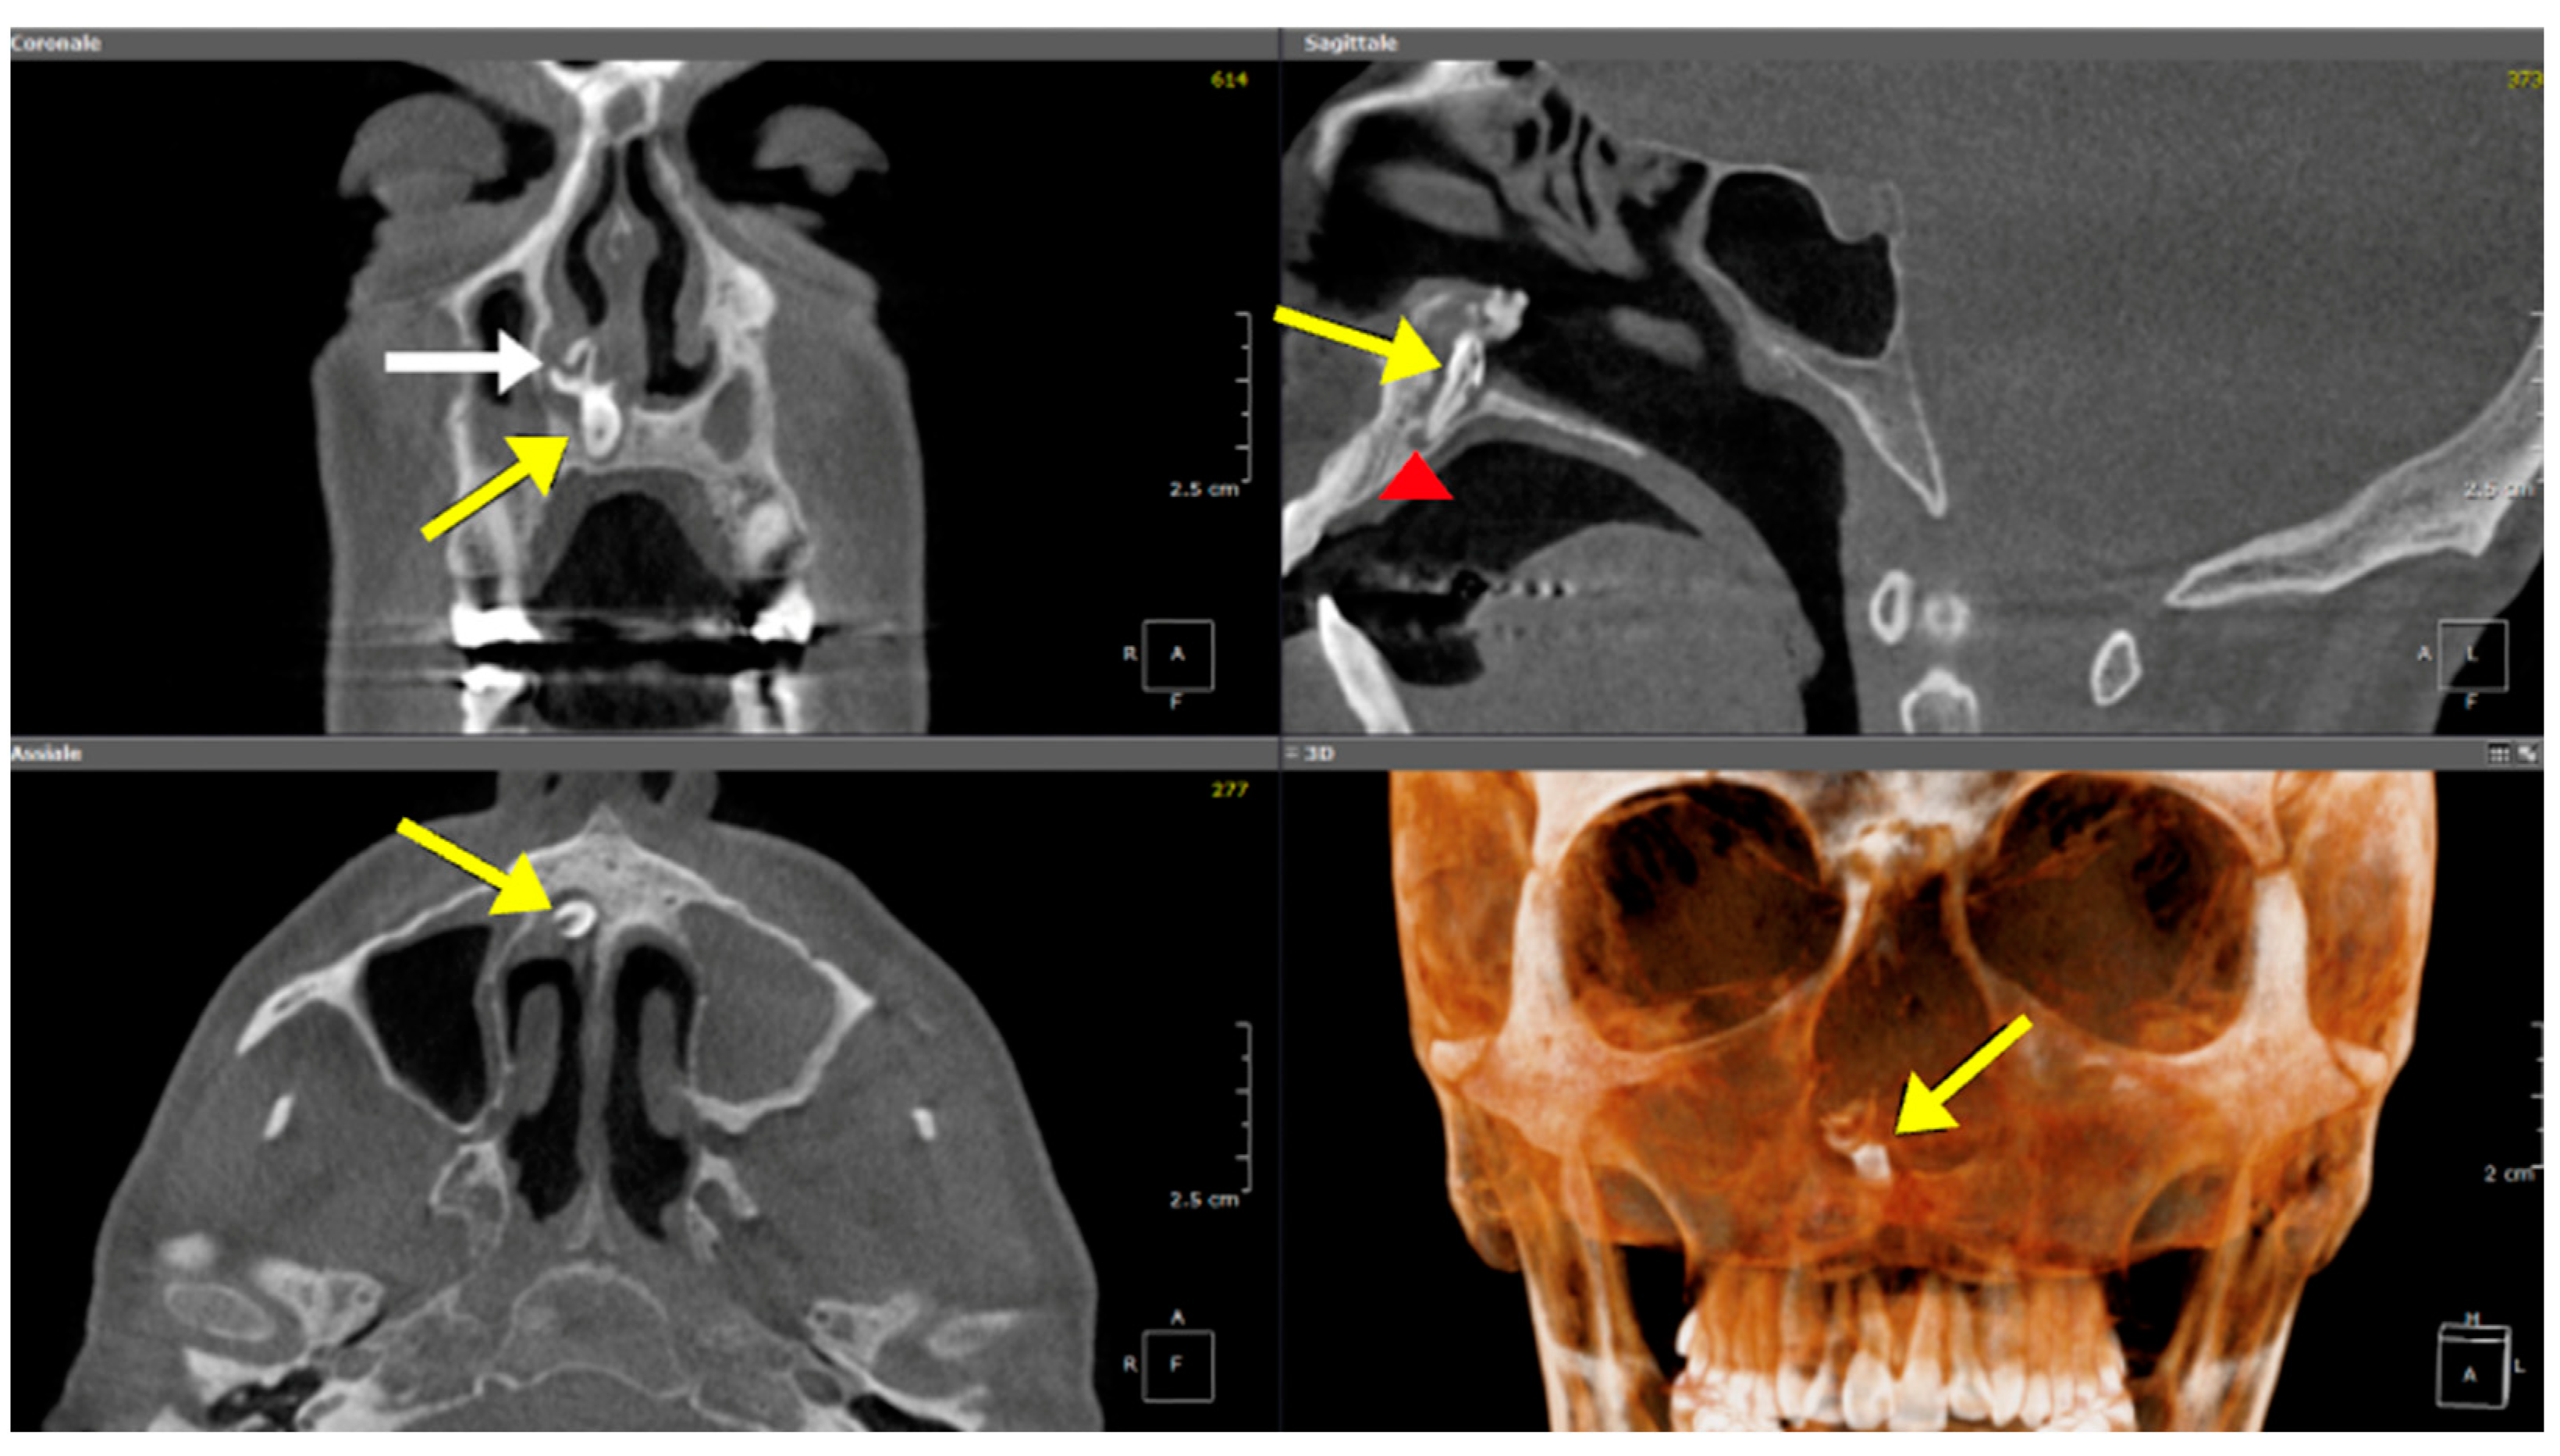

3.1.3. Inverted Mesiodens